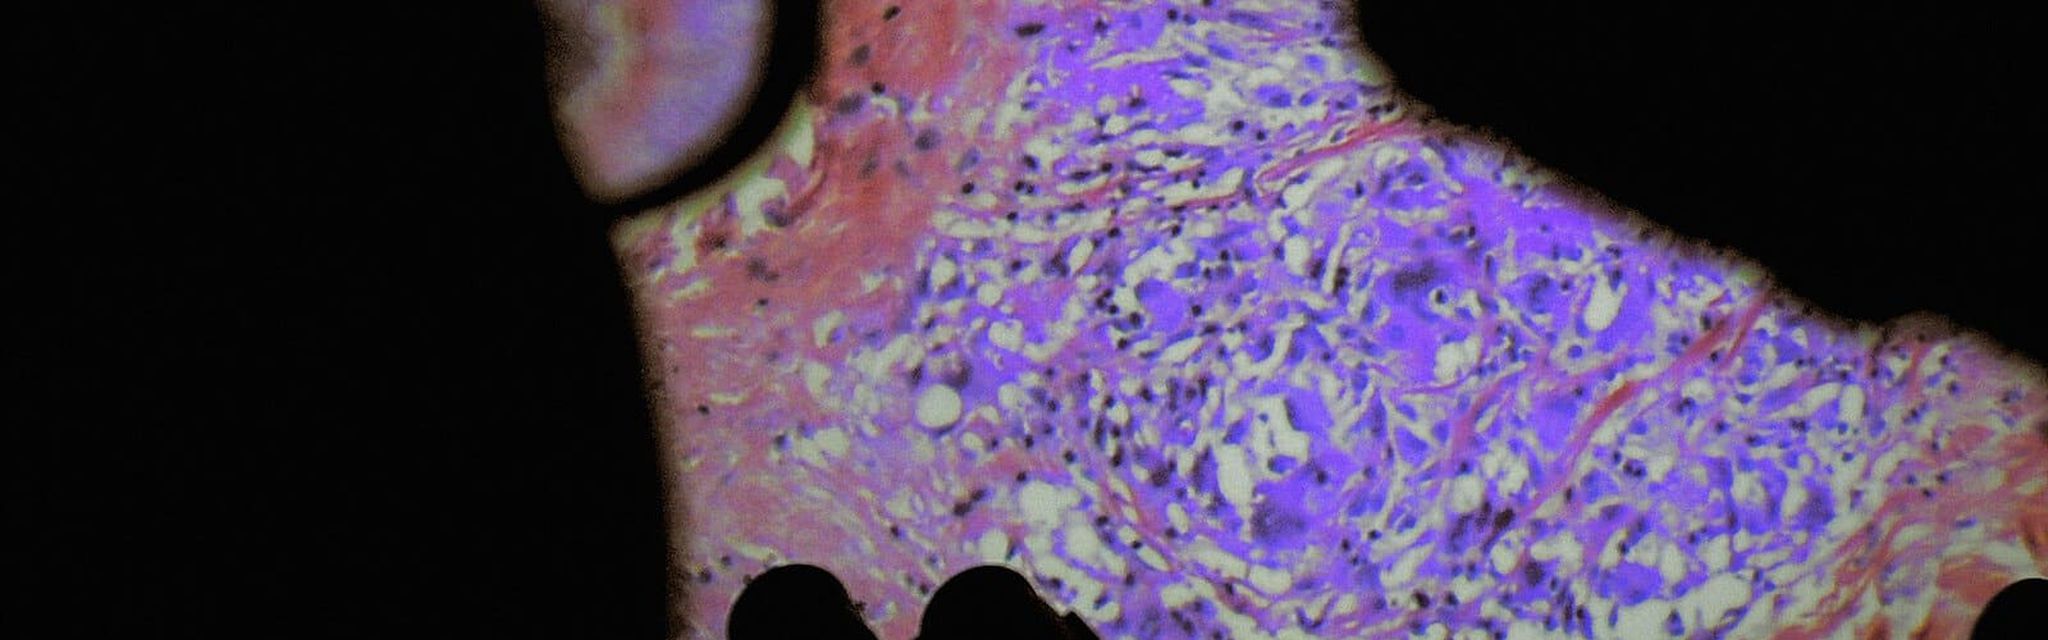

《人體萬花胴》電影海報

解剖學發明以降,人體奧秘開始為世人所知所見。然而,大家習慣的始終是那副最表面的臭皮囊,或留戀或厭倦,或擁抱或憎惡。假如能深入體腔,即時觀察微肌細理,體液流動,可會了悟箇中奧妙,那欲肉不為肉所欲的真義?得到醫院前線及技術人員協助,韋蓮娜柏麗芙與路西安卡斯當泰來再現了內窺和微創手術的影像,輔以病人和醫護的生活點滴,讓作為關懷、痛苦、希望和被宰制場所的身體,成了光影景觀的主角。血肉不再模糊的結果,可會對人文多一份凝視?